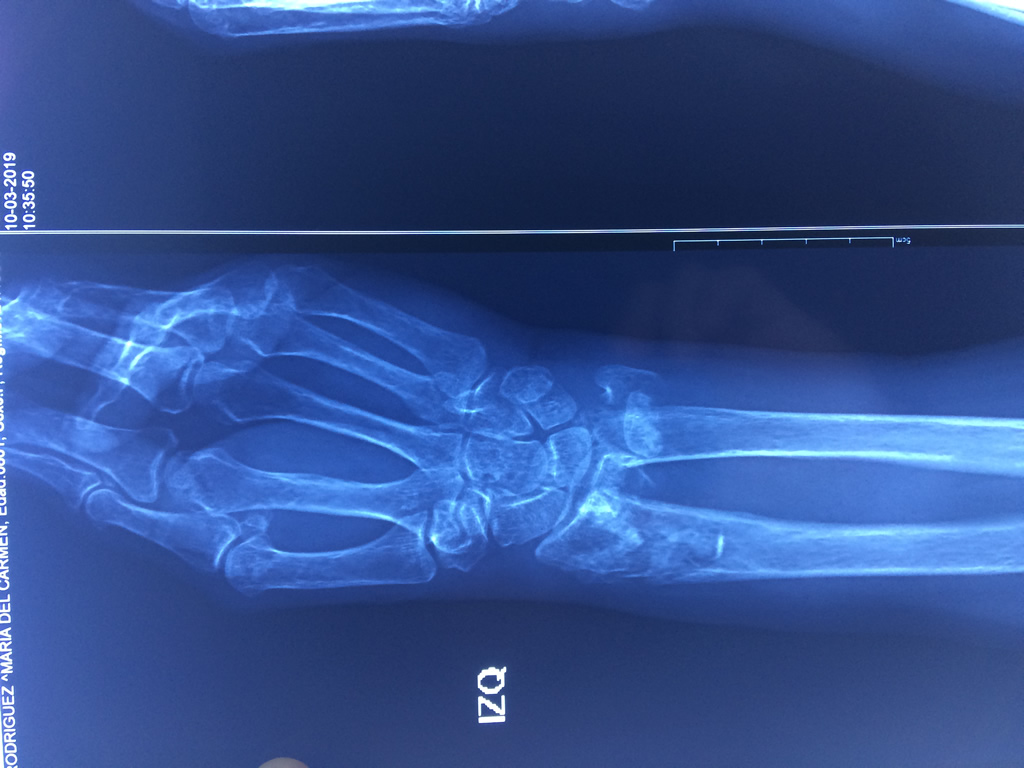

Cirugías de Hombros - Cirugías de Muñecas y Manos

Los procedimientos más comunes en cirugía de la mano son aquellos destinados a reparar traumatismos, incluyendo lesiones de tendones, nervios, vasos sanguíneos, y articulaciones; huesos fracturados; y quemaduras, cortes, y otros daños de la piel.